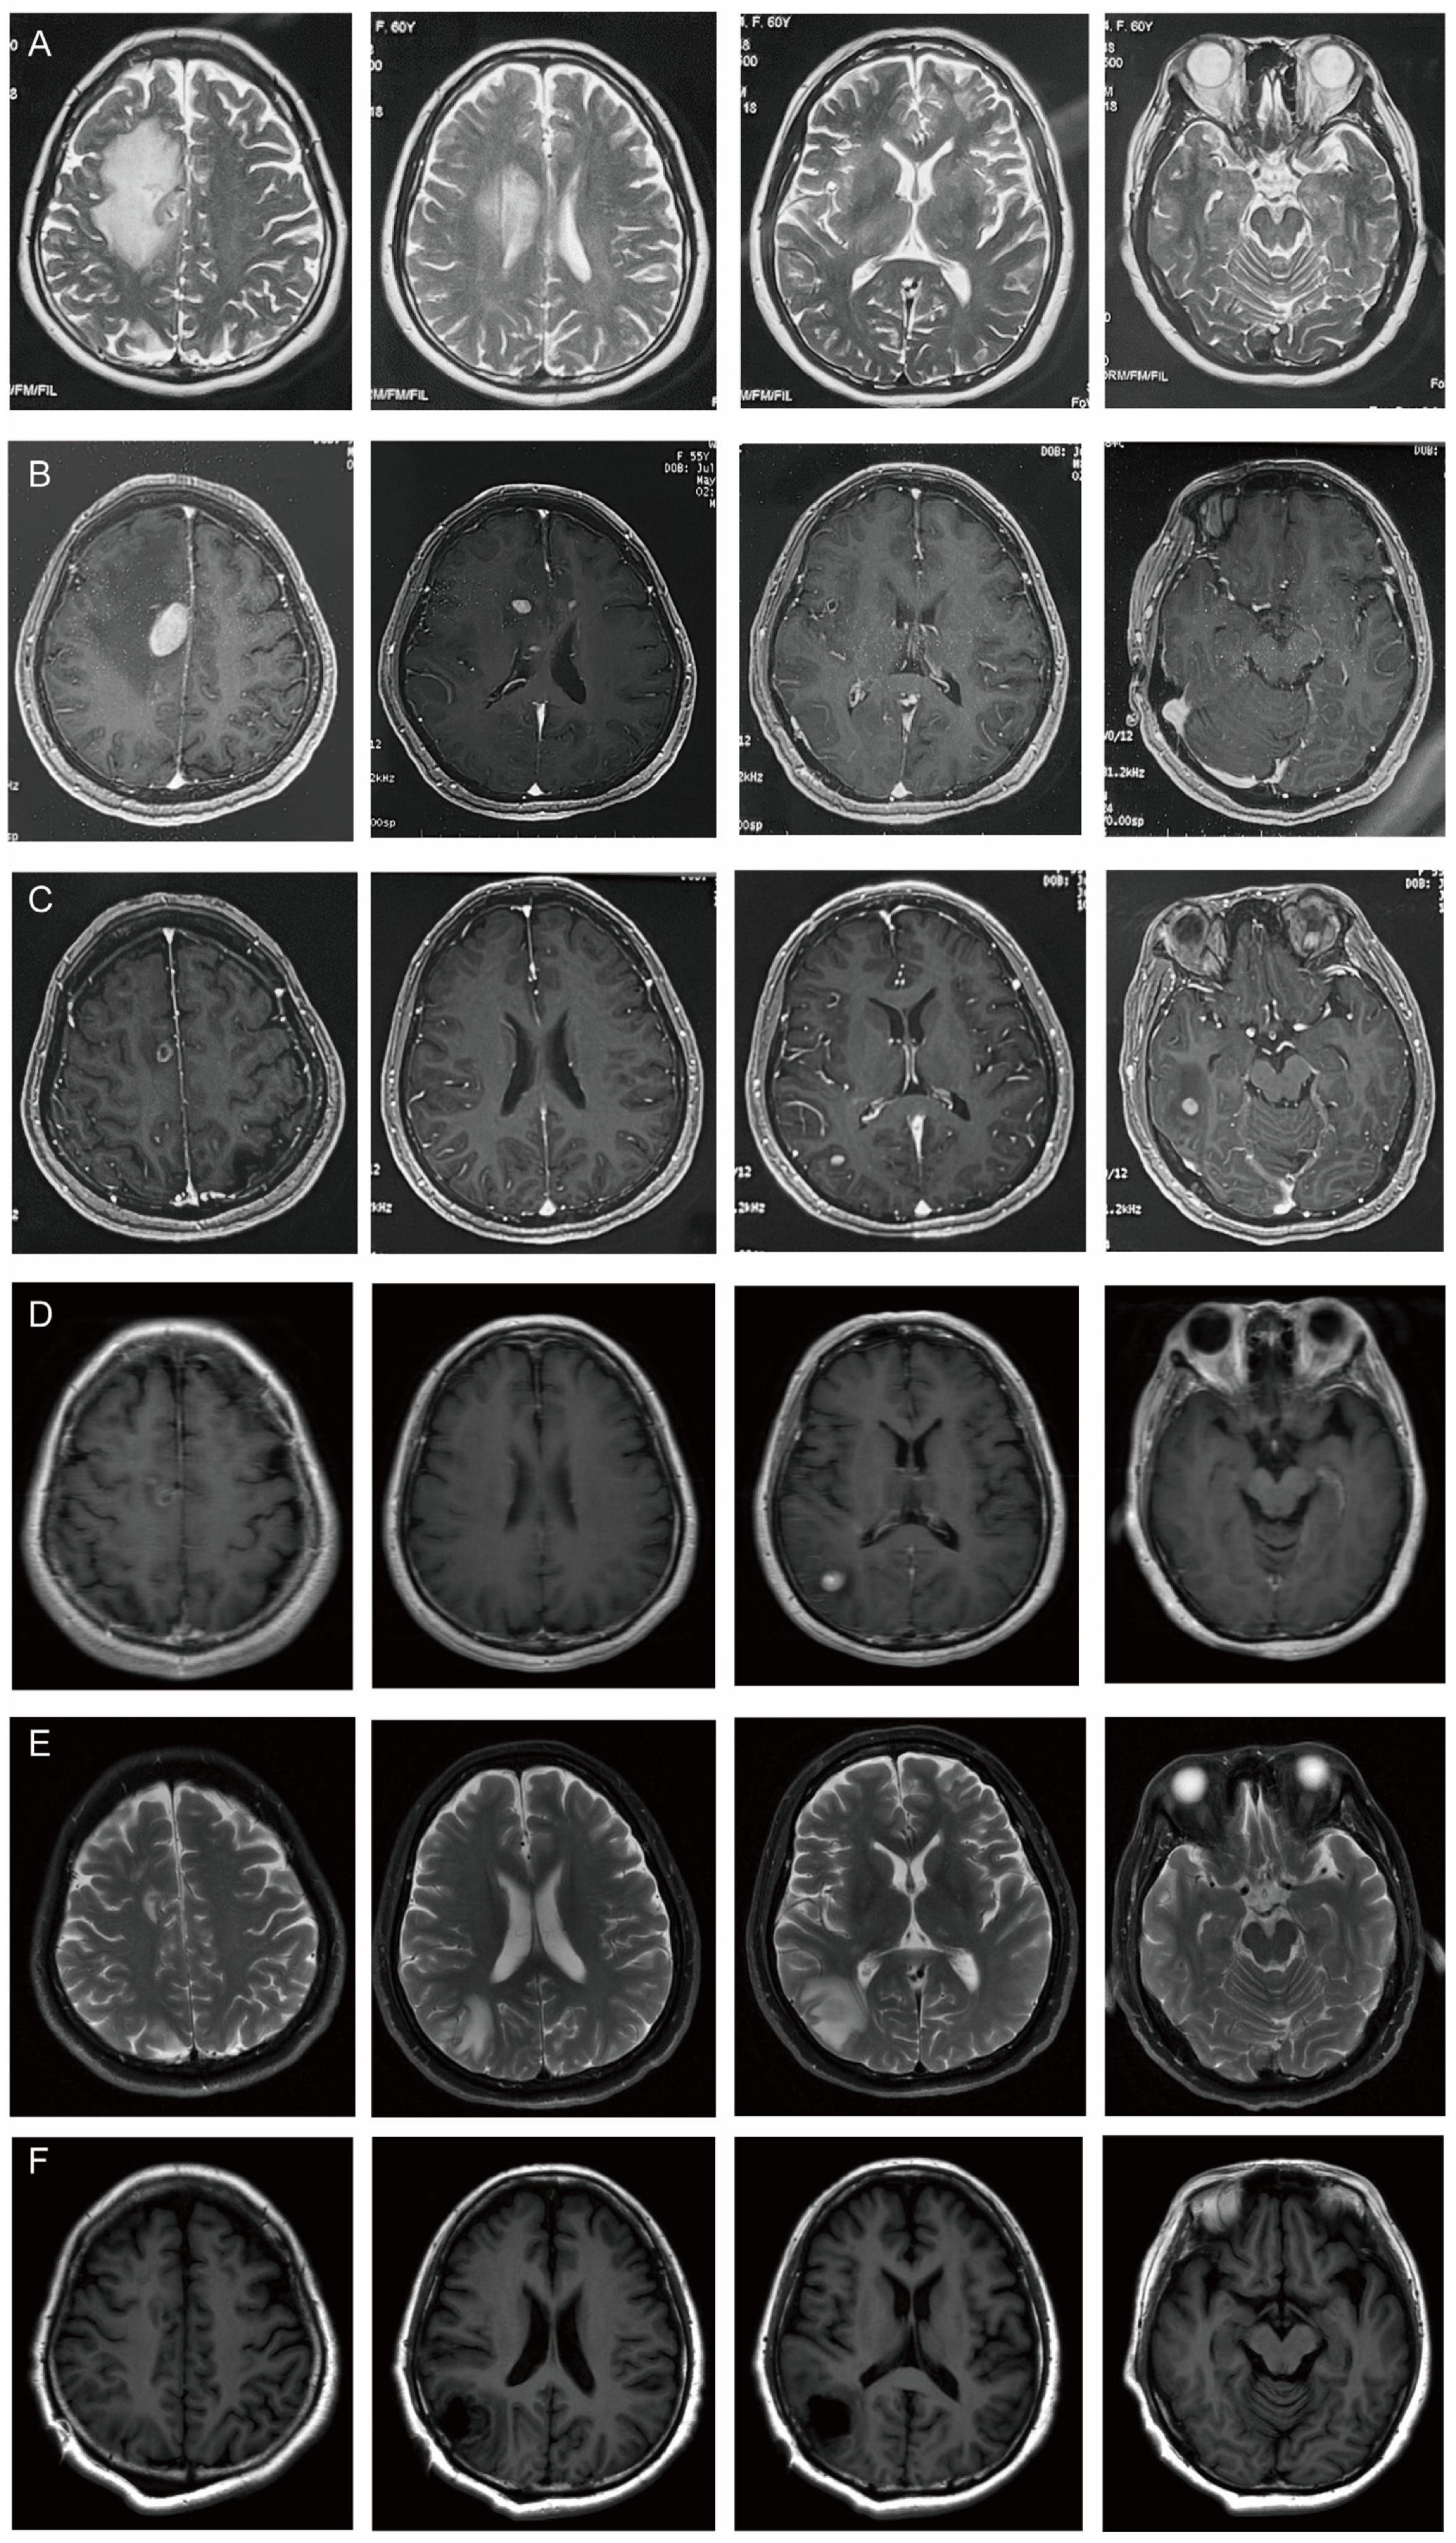

| MRI (4.18): nodular abnormal signals in the right frontal lobe of the brain next to the anterior horn of the lateral ventricle. It was considered to be metastatic tumor accompanied by peripheral odema. | |

| 6 May 2024 | MRI (5.6): multiple intracranial lesions in the right frontal lobe and top of the lateral ventricles. |

| 24 June–9 July 2024 | MRI (6.24): The lesions in the right frontal lobe and the top of the lateral ventricle reduced, but new lesions appeared in the right temporal lobe and occipital lobe. |

| MRI (7.9): Right temporal lobe lesions were smaller, but right occipital lobe lesions were larger. | |